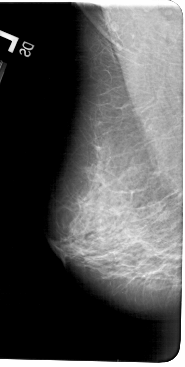

A_1602_1.RIGHT_MLO

LEFT_MLO LINES 5491 PIXELS_PER_LINE 2761 BITS_PER_PIXEL 12 RESOLUTION 43.5 NON_OVERLAY